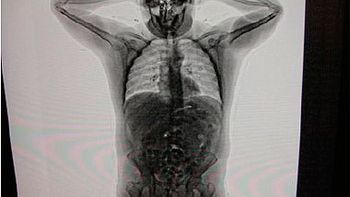

Dos mujeres fueron detenidas por trasladar paquetes de cocaína y, una de ellas con ingesta de cápsulas, durante dos operativos en la localidad tucumana de Trancas.

Las cápsulas, ocultas en el su equipaje y en los pañales del bebé, fueron halladas a partir de las contradicciones en las que incurrió la mujer al ser interrogada por los gendarmes durante el control, y

ante la intensificación de la requisa, la pasajera dijo haberlas ingerido también.